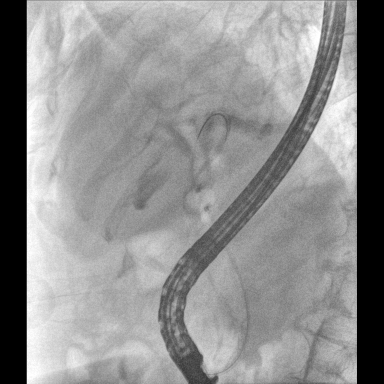

具備血管造影及數(shù)字減影(DSA)、路徑圖(Road-map)、透視、攝影等功能。 廣泛適用于介入科、血管外科、腫瘤科、消化內科及骨科等多個臨床科室,典型應用包括:TACE(肝腫瘤栓塞與化療灌注術)、心臟起搏器置入術、四肢動脈造影術、下肢靜脈濾器置入術、ERCP(經內鏡逆行胰膽管造影術)等。

核心DSA軟件可實時生成高清血管影像,結合路徑圖功能,在手術中為醫(yī)生提供血管導航。

設備搭載自主研發(fā)的大功率高壓發(fā)生器、高熱容球管與大尺寸平板探測器,配合先進圖像處理算法及高效冷卻循環(huán)系統(tǒng),能夠在長時間手術過程中持續(xù)輸出高清圖像并保持幀率穩(wěn)定。

預留高壓注射器聯(lián)動接口,C形臂開始透視時,高壓注射器自動注入造影劑,提高術中造影減影效率,減少醫(yī)師手推造影劑所受到的輻射暴露劑量。